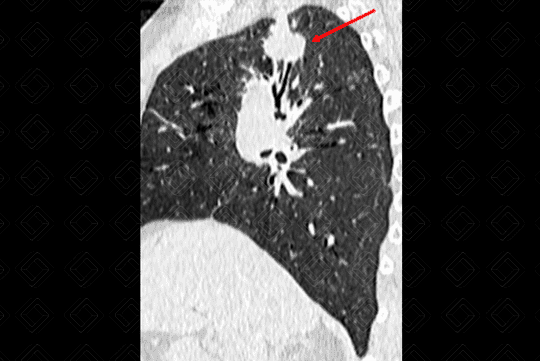

Texto alternativo para a imagem Figura 1. Créditos: Dra. Elazir Mota - Rio de Janeiro/RJ

Descrição das figuras 1, 2, 3 e 4: Tomografia computadorizada do tórax, seguida de reconstruções axiais e sagitais. Massa pulmonar, com contornos espiculados, localizada no segmento apical do lobo superior direito, medindo 3,2 cm x 1,5 cm x 2,2 cm (setas vermelhas).

Lembrando que, acima de 3 cm, a lesão já deve ser descrita como massa. Lesões menores que 3 cm são descritas como nódulos. Isso também é importante no estadiamento TNM (lesões ≥ 3 cm já são consideradas pelo estadiamento como T2).